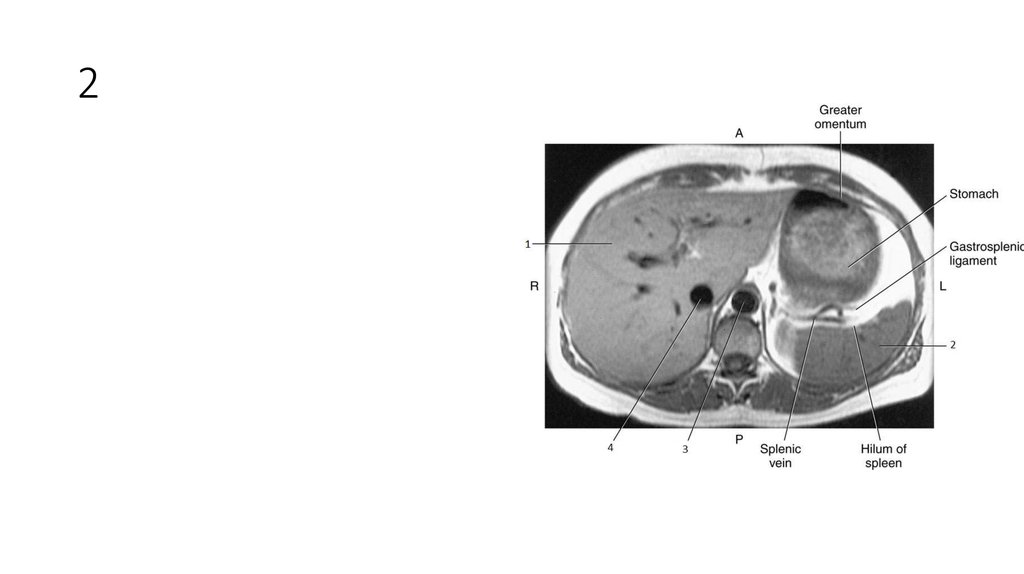

10. 1

11. 1

• Right Adrenal Gland

12. 2

13. 2

• Spleen

14. 3

15. 3

• Liver